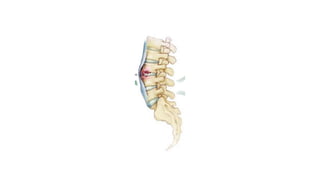

In clinical practice, it is customary to

explain,

Central Type of vertebral body

involvement,

“skipped lesions”

due to spread along Batson’s plexus of

veins

Typical paradiscal lesions and

vertebral lesions

due to spread by way of arteries.

Anterior Type

due to extension of an abscess

beneath the anterior longitudinal

ligament and the periosteum.

PARADISCAL CENTRAL ANTERIOR POSTERIOR